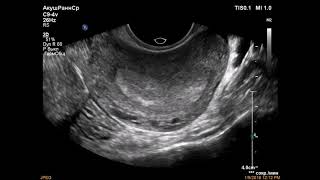

🌠 Стимуляция овуляции